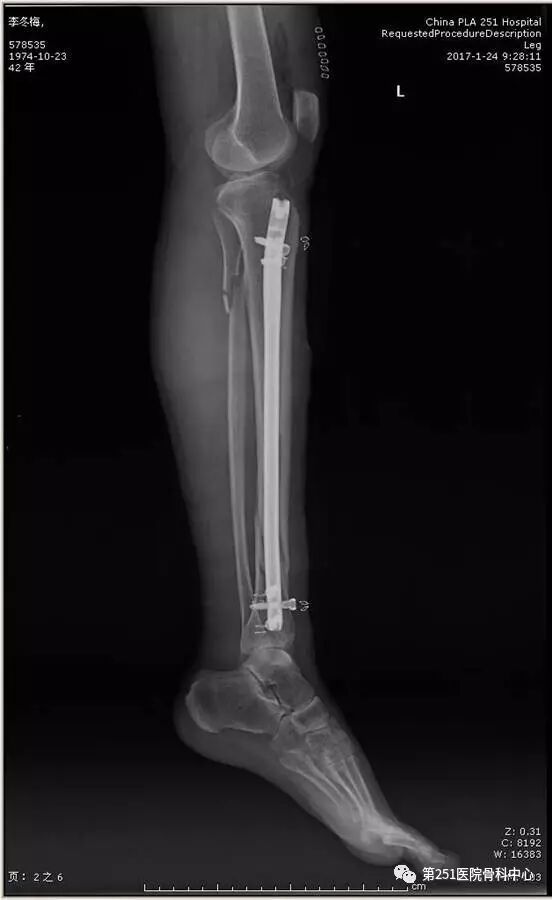

病例4:女性,车祸伤,同侧股骨、股骨颈合并胫腓骨骨折。

![]()